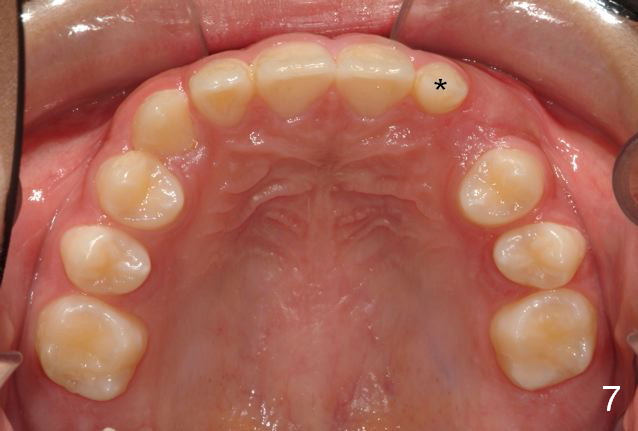

A 11-year-old boy has shorter lower 1/3 face (Fig.1,2) with light concave profile, especially the lower lip (Fig.3).  There is anterior deep bite (Fig.4) with Class II posterior occlusion (Fig.5,6).  UL2 is microdontia (Fig.7 *), while the Lower Es are retained (Fig.8).  Preop (2015_01_07) Ceph (Fig.9) and Pan (Fig.10) show ectopic L7s and congenitally missing L5s.